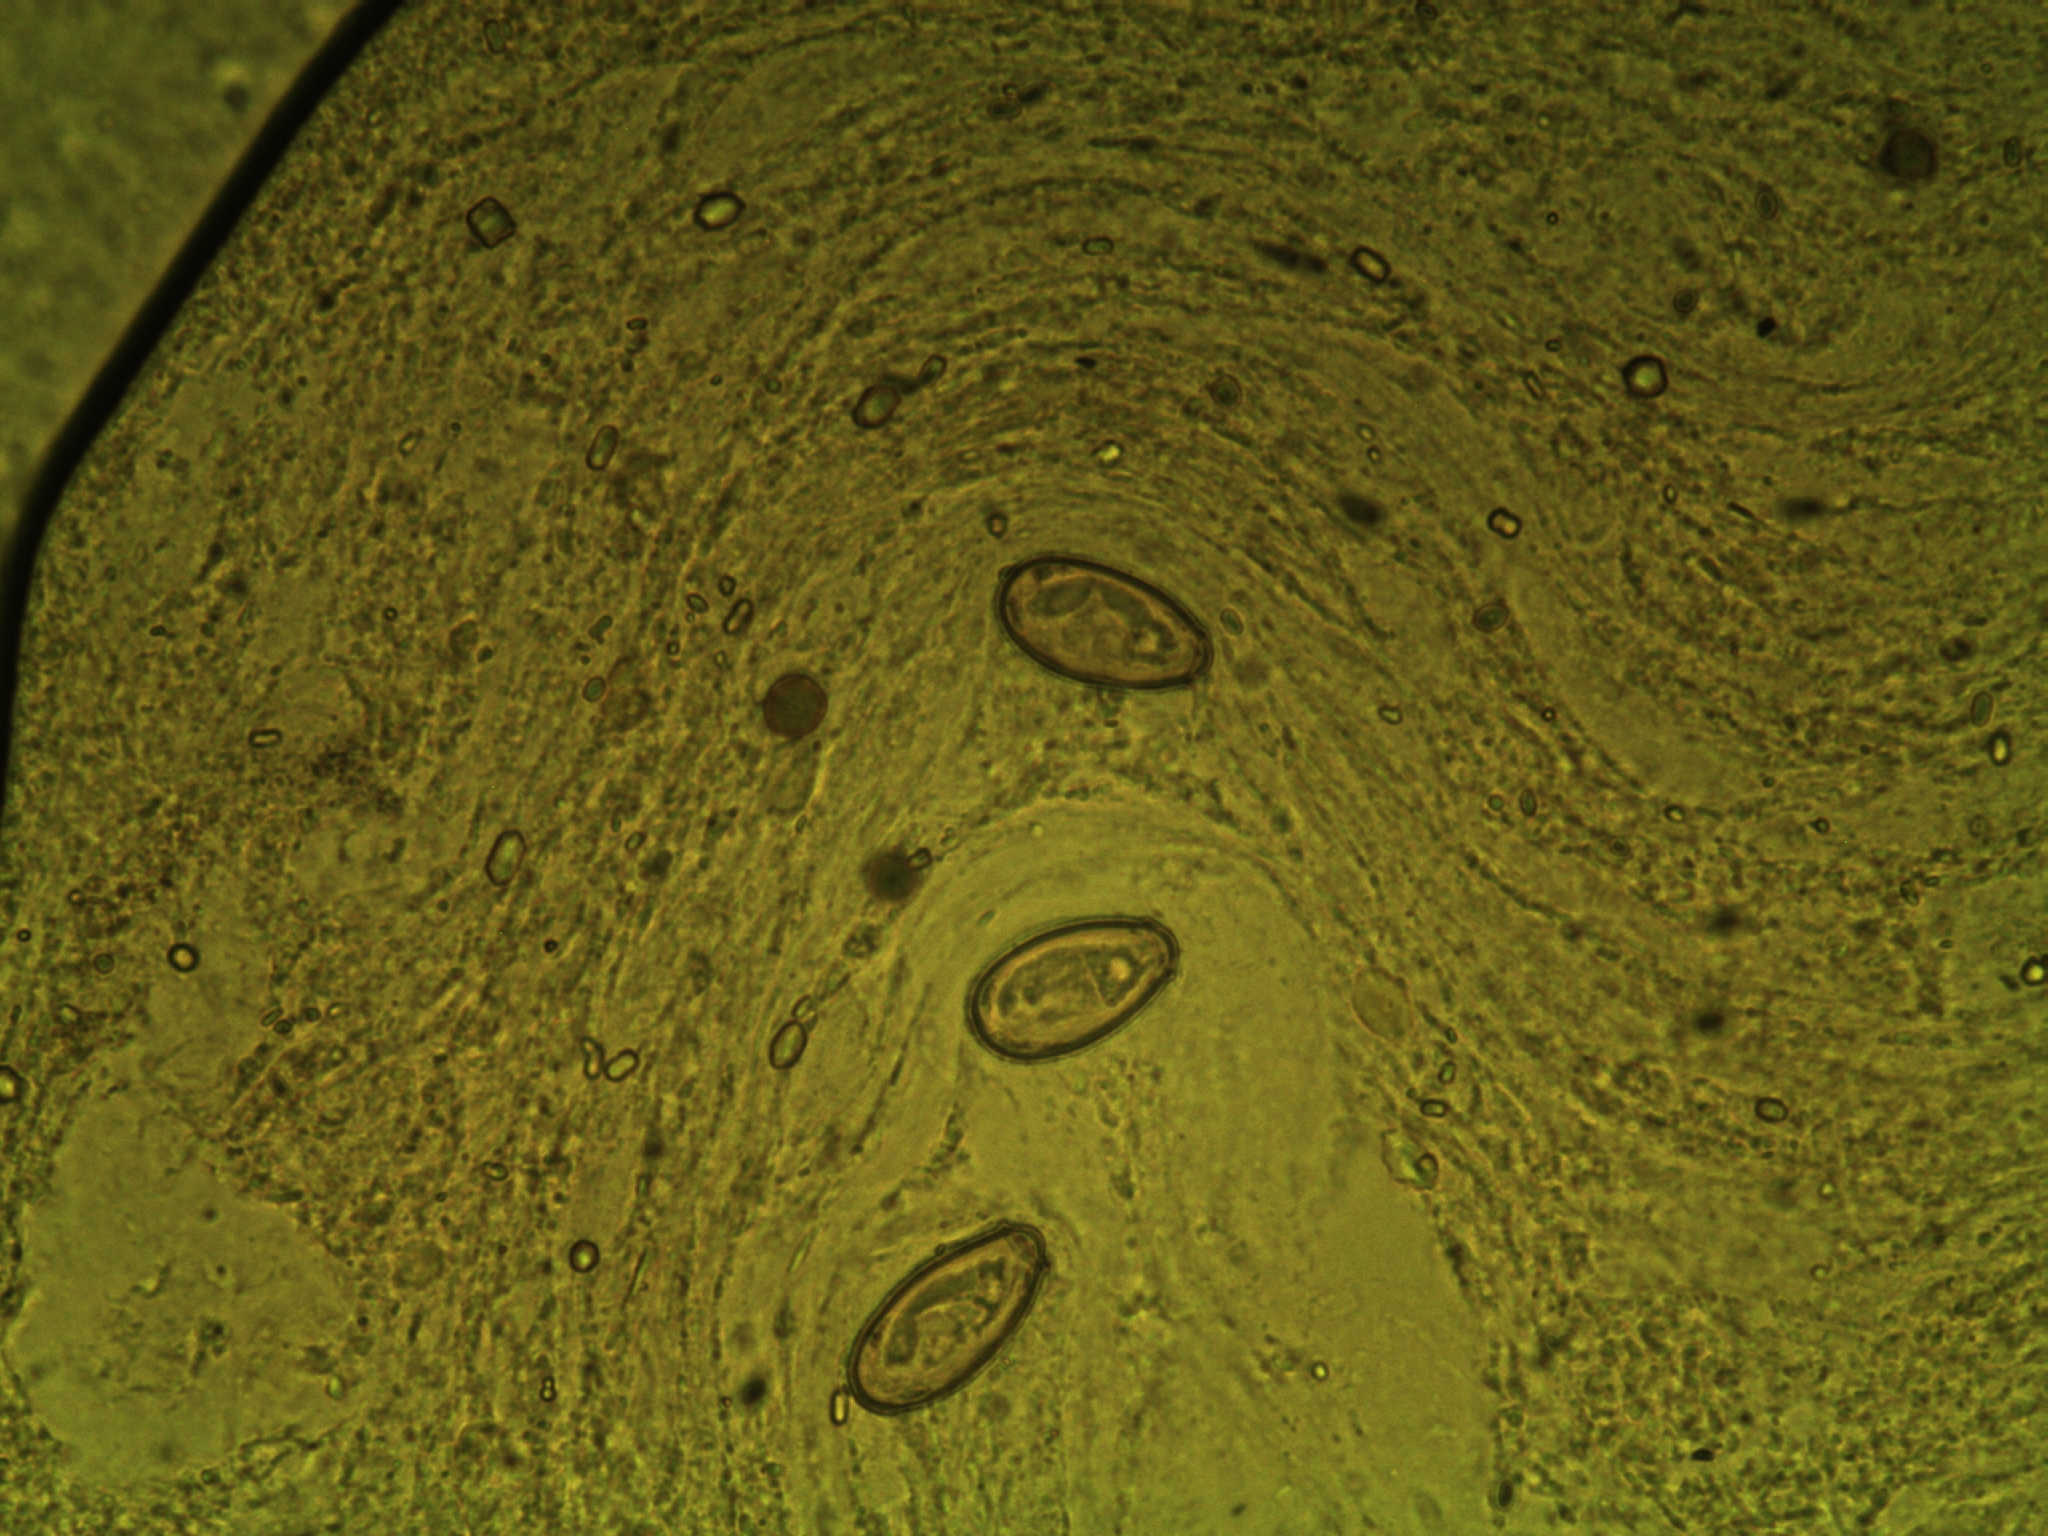

病犬常呈慢性经过,表现长期消化不良,异嗜,食欲减退,前期便秘,后期腹泻,间歇便秘或下痢交替出现,渐进性消瘦,可视粘膜苍白黄染;病的后期出现腹水,腹围膨大,扣诊呈水平浊音,上界随着体位的变化而变化,腹腔穿刺后有透明液体流出;病犬常呈站立姿势或犬坐姿势,呼吸困难,有的可触摸到肝脏肿大;实验室检查常见贫血、总胆红素、碱性磷酸酶升高;粪便镜检可确诊如图: